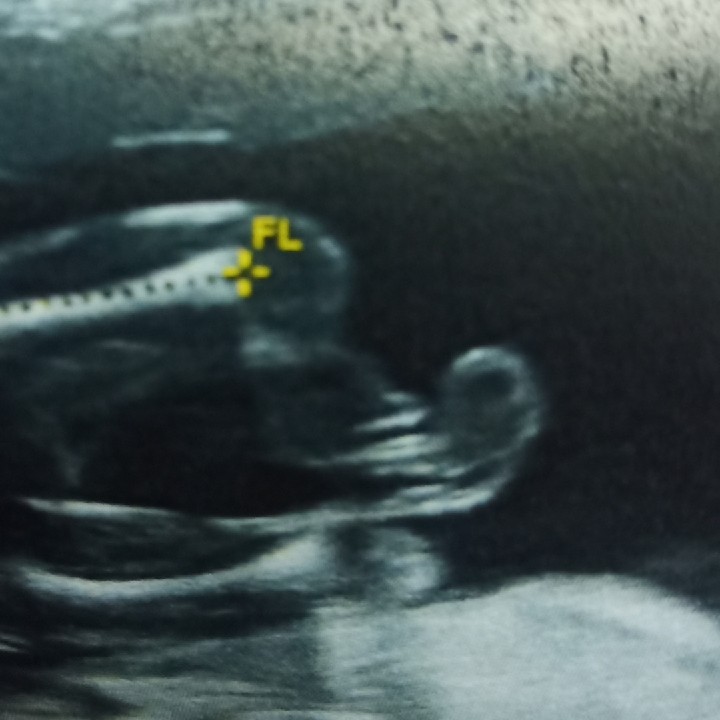

3เดือนแล้วค่ะ..เริ่มเห็นแขน ขา บ้านใหนเหมือนกันมั๊ยค่ะ???3เดือนเห็นชัดขนาดนี้เหมือนกันรึป่าวค่ะ

12 week ค่ะ เพิ่งซาวน์เมื่อวานนี่เอง 😊

ของเรา14wค่ะ ไปซาวด์มาเมื่อวาน 😄😄

12วีคจ้า ปัจจุบัน25วีคแล้วค่ะ💕